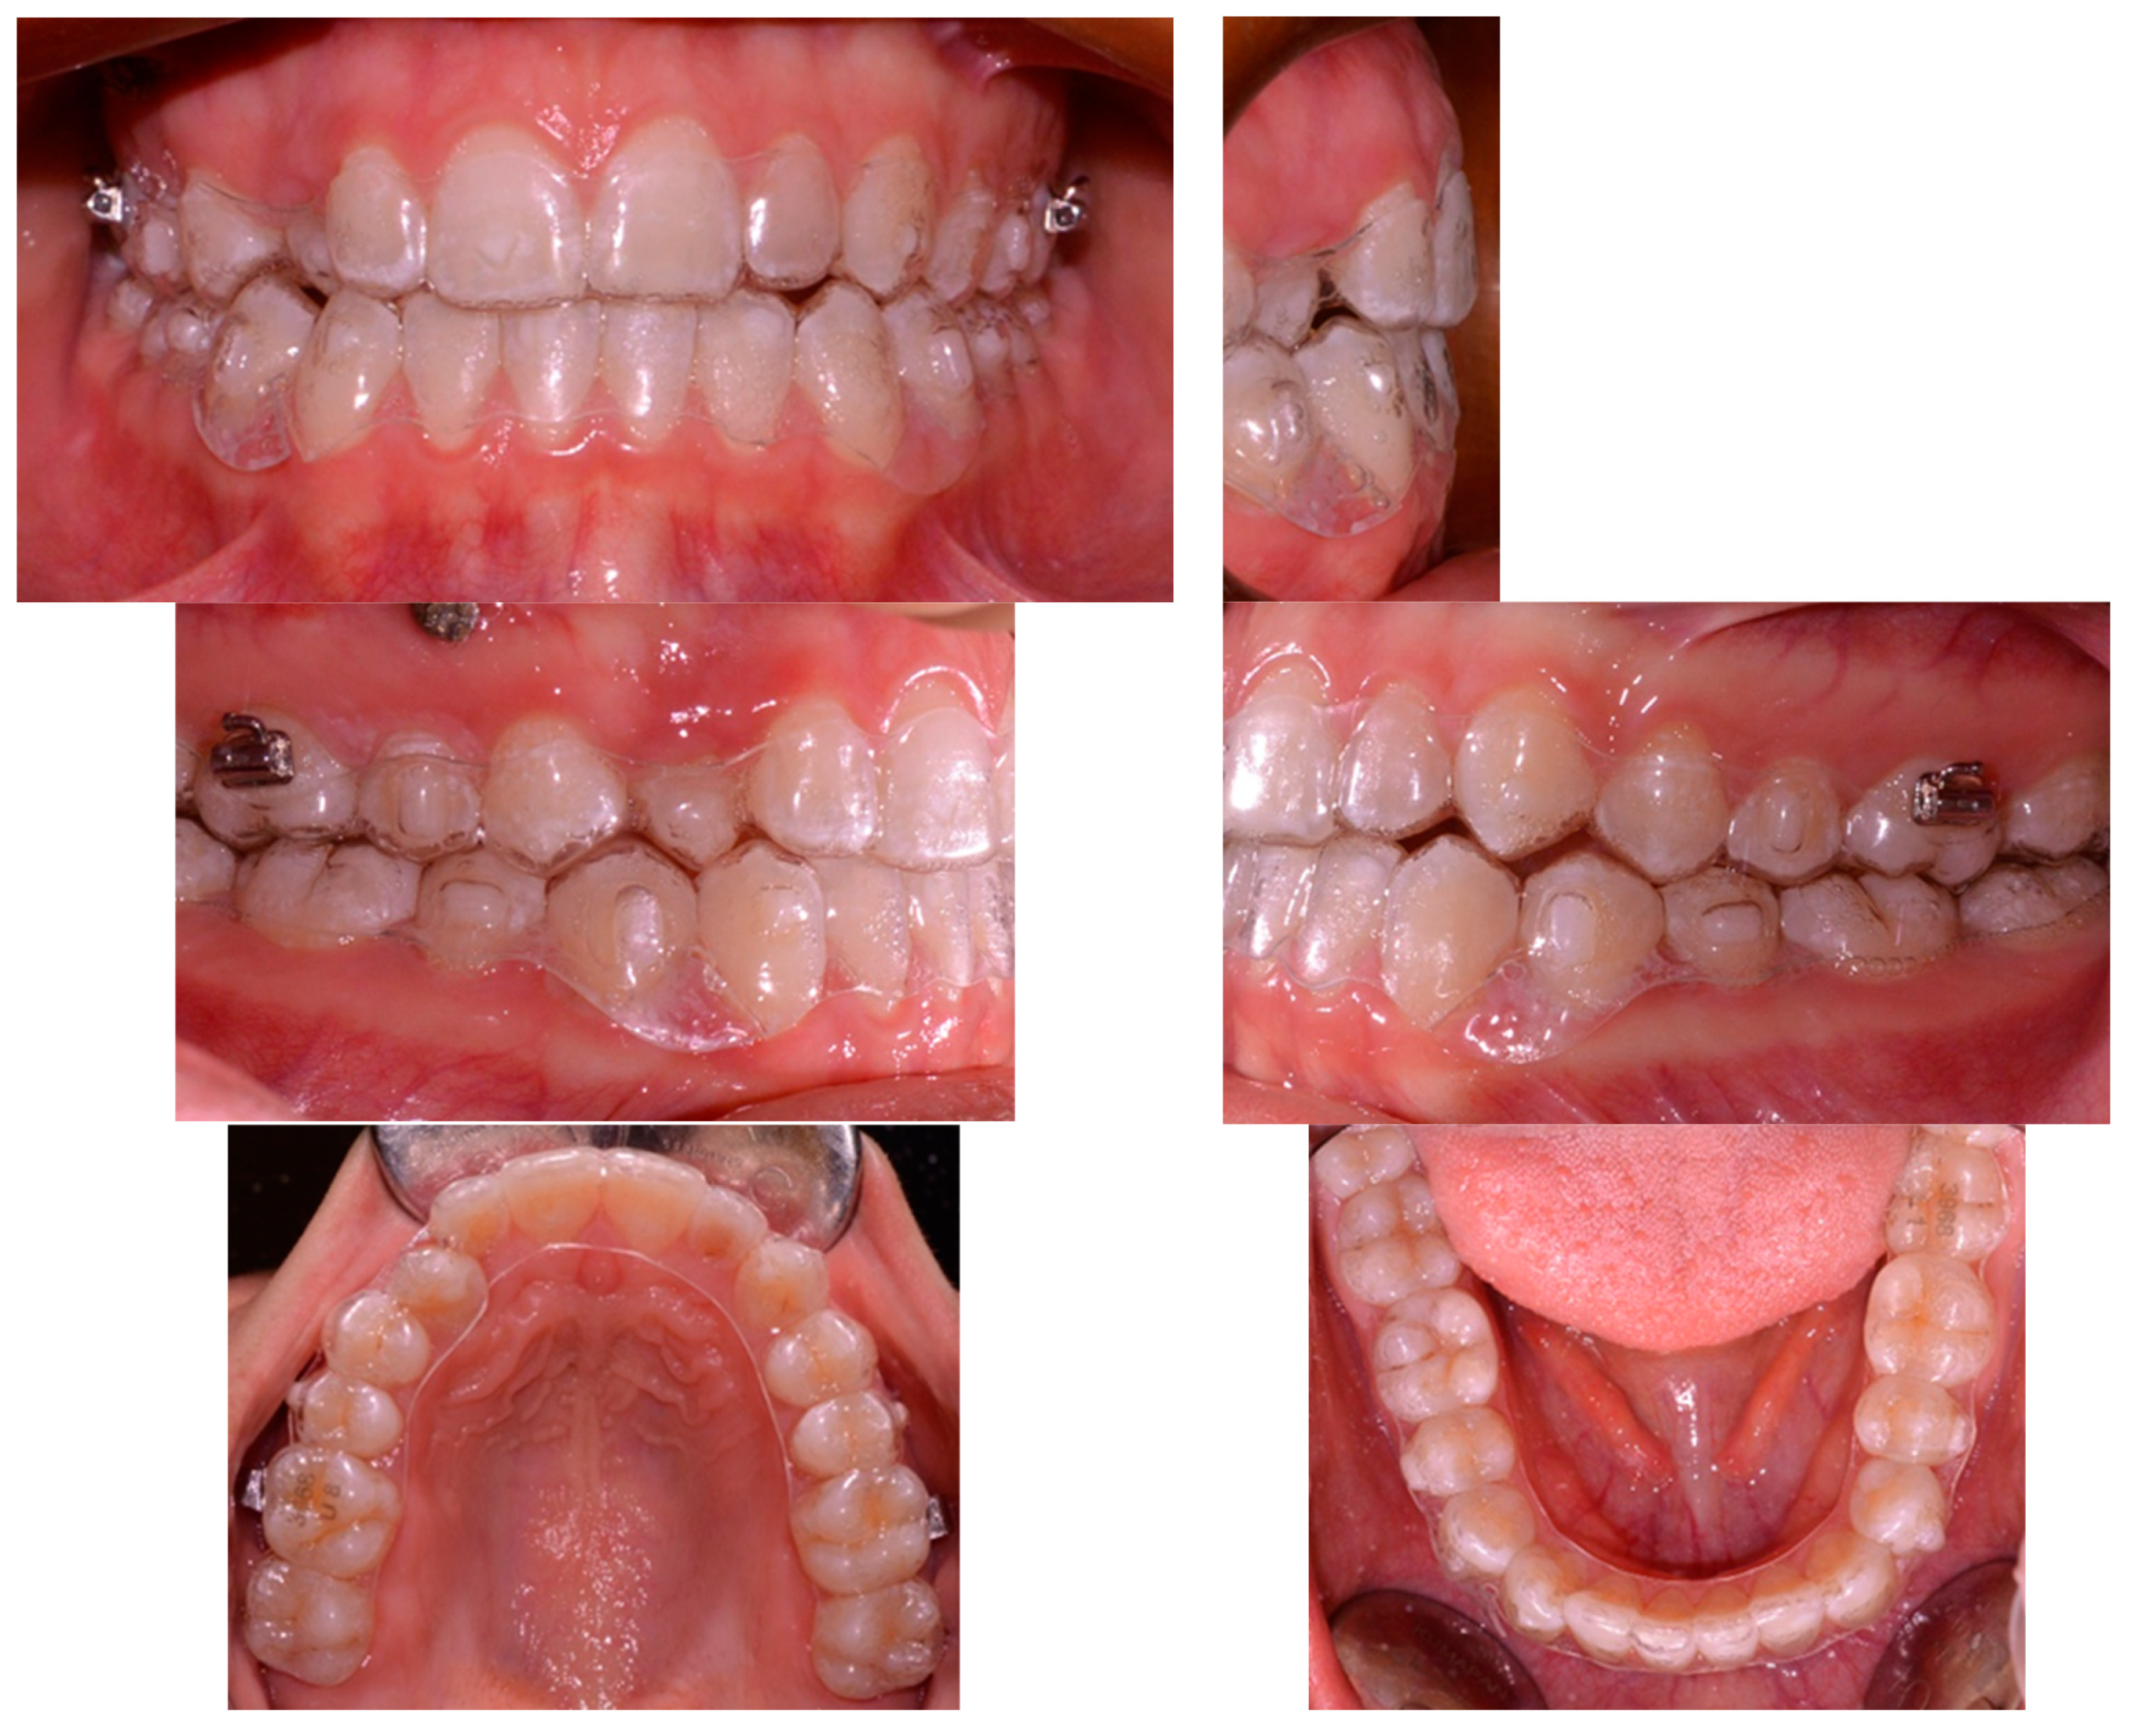

2.1. Clinical Case